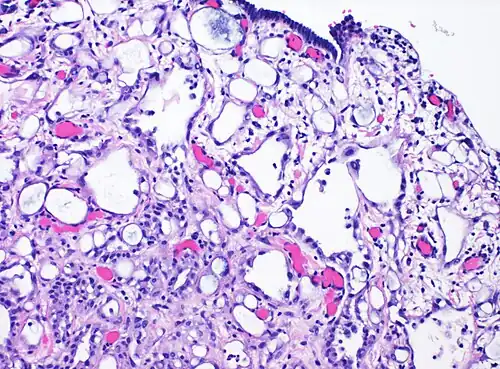

| High-magnification micrograph of an adenomatoid tumor. H&E stain. | |

High magnification of the same case, showing the typical[9] features of tubular spaces of varying size composed of flattened cells resembling endothelium.